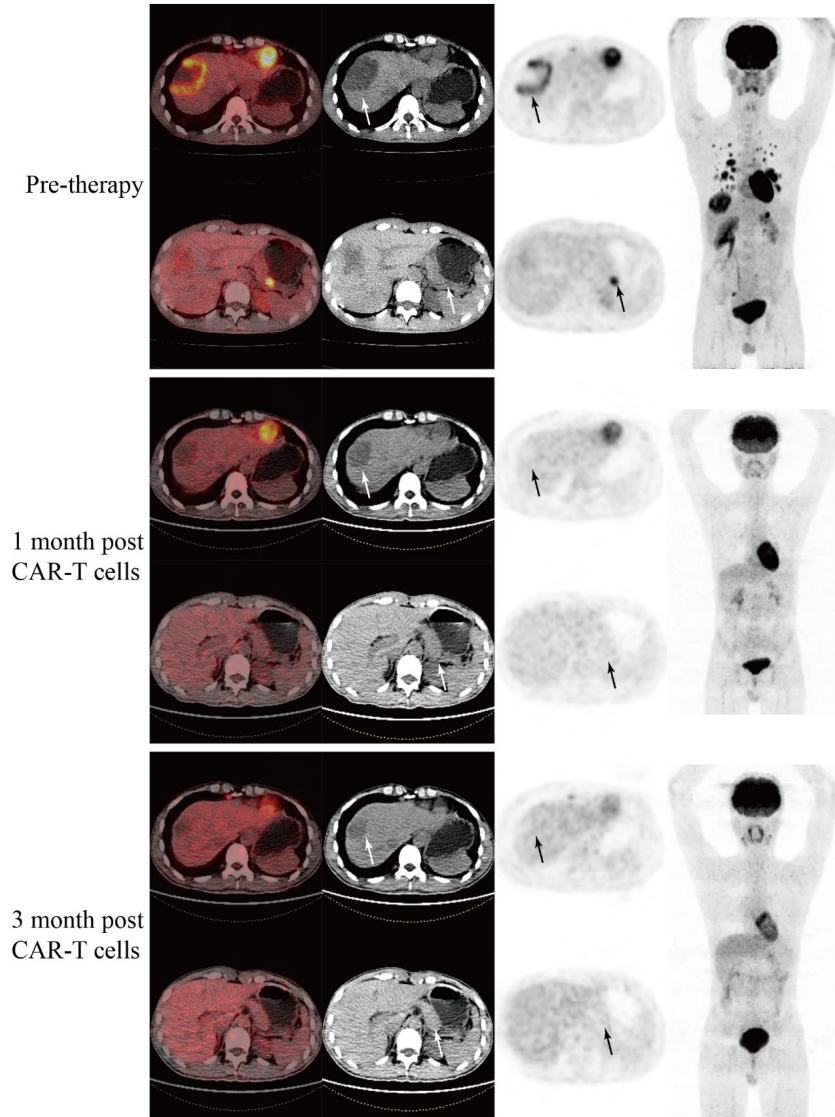

Three months post-treatment, the metastatic lesions (including liver and pancreas) showed no FDG uptake, achieving partial remission

Three months post-treatment, the volume of liver metastases significantly reduced, and the liver lesions showed no FDG uptake, achieving partial remissionLatest research results presented at the 2025 Gastrointestinal Cancer Symposium showed that researchers evaluated two different doses of GCC19CAR-T. In dose group 1 (1 x 10⁶ cells/kg), 4 evaluable patients were included, with an overall response rate (ORR) of 25.0%, where 1 patient achieved confirmed partial remission (PR), and 2 patients showed partial metabolic remission with stable disease (SD); while the performance in dose group 2 (2 x 10⁶ cells/kg) was even more impressive, with an ORR of 80.0% among 5 patients, where one fortunate patient had all tumor target lesions disappear, achieving pathological complete remission! Three lesions significantly reduced, achieving partial remission, and another patient showed complete metabolic remission in PET/CT examination. Overall, across both dose levels (9 patients in total), the ORR reached 56%. The disease control rate was 75% in dose group 1 and 80% in dose group 2, with an overall disease control rate of 78%.